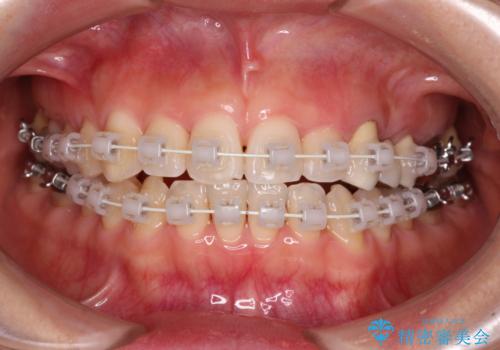

- 審美装置

装着されているブリッジを切断して矯正治療を行うことや、手間をかけずに早めに治療を終えたいとのことで、目立たないワイヤー装置による矯正治療を行うこととしました。

矯正治療中に上下前歯が接触しない時期があり、咬み合わせ改善のために期間がかかるのではないかと懸念されましたが、結果的には補綴治療も含めて1年以内の短期間で終えることができました。